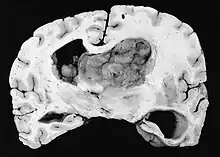

Subependymal giant cell astrocytoma (SEGA, SGCA, or SGCT) is a low-grade astrocytic brain tumor (astrocytoma) that arises within the ventricles of the brain.[1] It is most commonly associated with tuberous sclerosis complex (TSC). Although it is a low-grade tumor, its location can potentially obstruct the ventricles and lead to hydrocephalus.

a,b)Images of subependymal giant cell astrocytomas arrowheads

Diagnosis is made by imaging with a contrast-enhanced MRI or CT scan of the brain.[3]